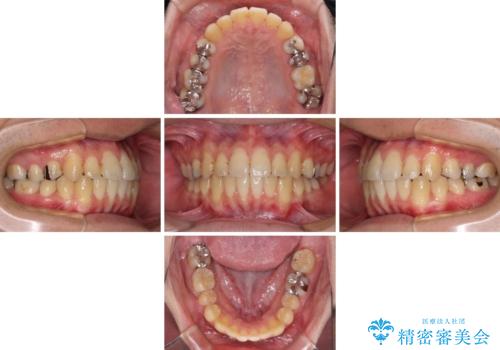

前歯のクロスバイトをインビザラインで矯正治療

- 前歯のデコボコとクロスバイトを気にして来院された患者様です。

前歯を早く整えたいとの希望があったので、ワイヤー矯正にて短期間でクロスバイトを解消し、その後インビザラインにて整えることとしました。

インビザラインによる前歯のクロスバイト改善におけるリスクとして、前歯歯髄充血・歯髄壊死が挙げられます。

ワイヤー矯正を併用する目的として、短期間でデコボコやクロスバイトを改善する他に、歯髄充血リスクを低減させるというものがあります。